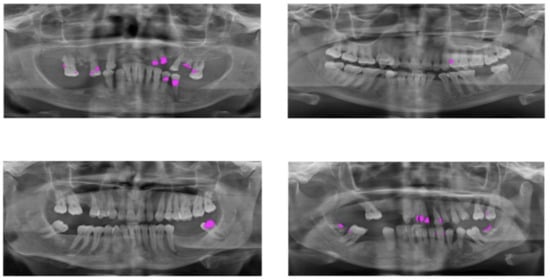

At first, two dentists (thanks to Noura A. Alrogaibah and Ghadeer K. Aljarbou from the Primary Health Care Government Center in Qassim for labeling and reviewing the ground truth of the dataset) marked the cavities in the images. All dentists were employees at the Ministry of Health in Saudi Arabia and had clinical experience of 5–8 years. As a result of marking images, only 510 of 1500 panoramic X-ray images have cavities. After marking the cavities in the dataset by dentists, the ground truth of the labeled dataset is generated using the ImageJ tool (https://imagej.nih.gov/ij/ (accessed on 20 August 2023)) [42]. The number of images from the cropped dataset is 673 with dimensions of 512 × 512 pixels. The annotation of the image showed that only 510 of the panoramic X-ray images of 1500 had cavities. Figure 2 presents some samples of the dataset after annotation of the cavities in the panoramic X-rays.

Figure 2. Sample panoramic X-ray images from Ivisionlab [41] after being annotated by two dentists. The cavity’s location on the panoramic X-ray image is shown by the pink color.